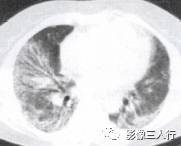

胸部影像常呈肺段或肺叶急性炎性实变。影像实变期表现为密度均匀的致密影,在实变 区中可见空气支气管征。其病理基础是由于广泛的肺泡腔内炎性渗出,肺充气明显减少,使 正常充气的各级支气管与实变的肺泡构成鲜明的对比,形成支气管充气征。见图4至图6。 医学百科网 | YxBaike.Com